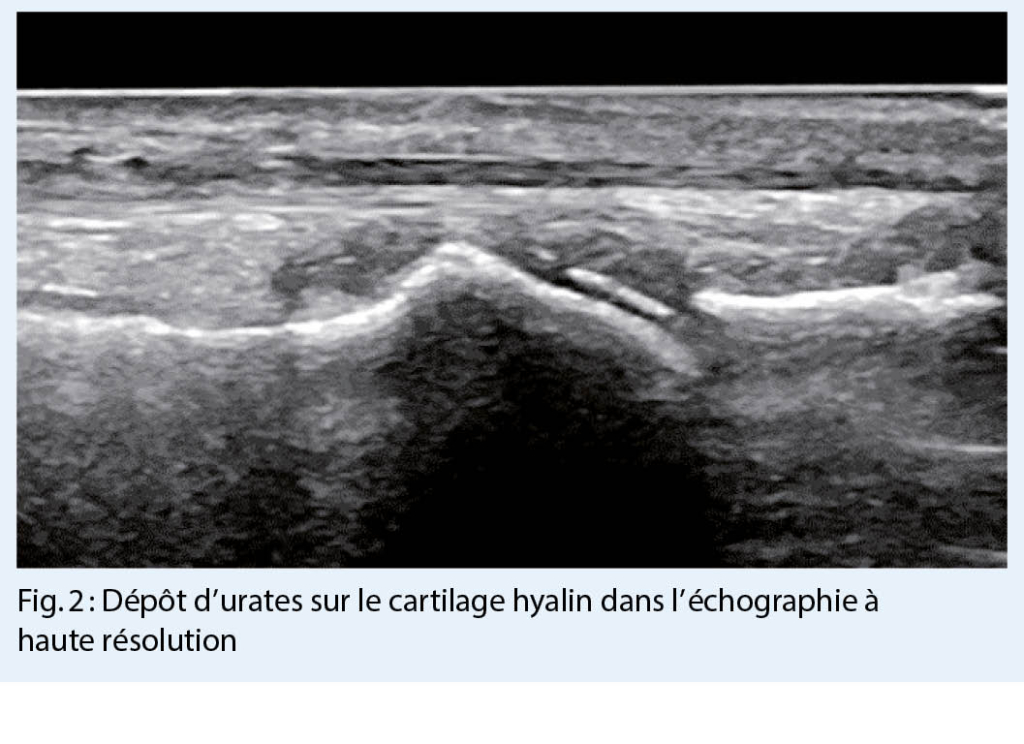

L’ arthrite goutteuse aiguë est généralement une monoarthrite qui se manifeste de façon suraiguë (avec des douleurs, des rougeurs et des gonflements importants) et affecte de préférence les membres inférieurs. Plus la clinique est typique, plus le diagnostic est probable. Cependant, le diagnostic différentiel doit toujours considérer une infection ou une pseudo-goutte (chondrocalcinose). Le gold-standard pour un diagnostic fiable reste la détection microscopique de cristaux d’ urates dans le prélèvement de l’ articulation affectée (fig. 1.) (ou celui du tissu) ou d’ identifier des dépôts d’ urates par échographie à haute résolution (fig. 2.) ou, à la rigueur, par tomodensitométrie à double énergie (les deux méthodes d’ imagerie sont très spécifiques, mais nécessitent un certain dépôt d’ urates pour être détectées et peuvent donc être faussement négatives, surtout dans les premiers stades).